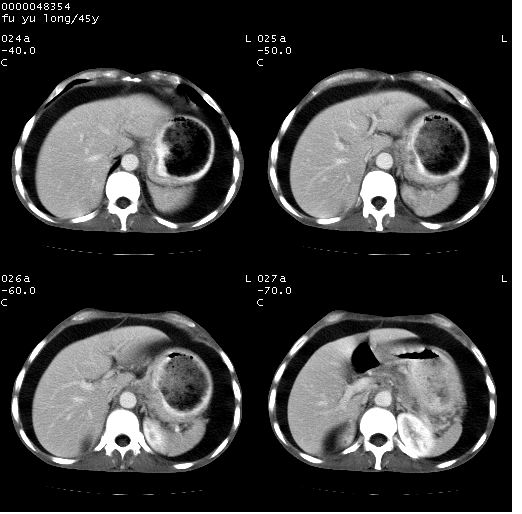

以下是引用lkc8963在2008-5-30 8:44:00的发言:[br]胃窦癌伴网膜(胃结肠韧带)/腹膜及腹膜后淋巴结转移.

以下是引用医影拾贝在2008-5-30 2:38:00的发言:[br]气肿性胃炎、胃十二指肠溃疡、腹膜炎,考虑穿孔可能性较大